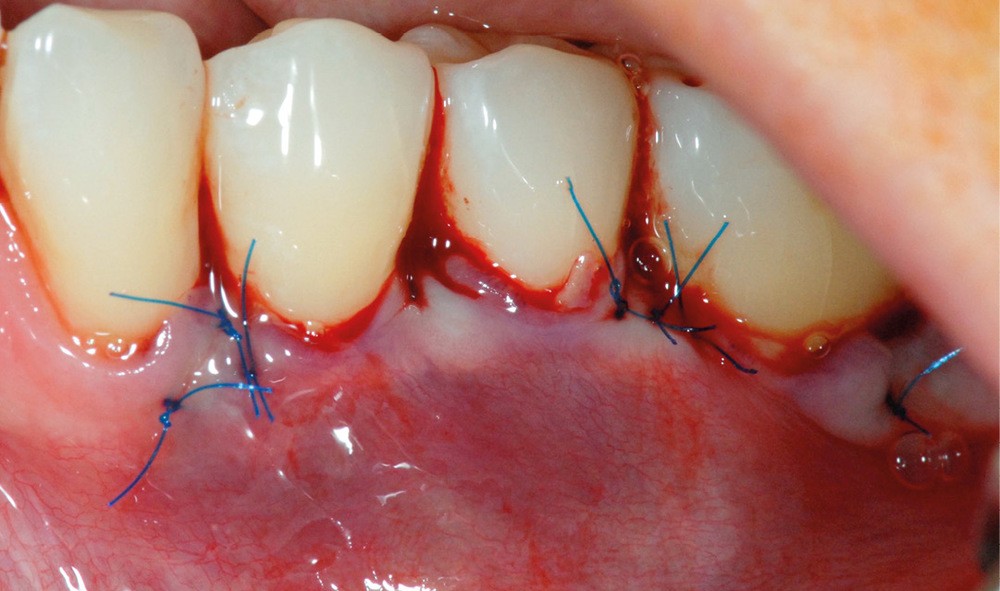

Cette technique permet de recouvrir des récessions gingivales contiguës par une traction coronaire après une dissection partielle superficielle au-delà de la ligne muco-gingivale. Grâce à un jeu d’incisions des papilles, les incisions de décharge ne sont pas nécessaires. Un greffon conjonctif prélevé au palais selon la technique de l’enveloppe [3] est placé sur les récessions et suturé en même temps que le lambeau par des points suspendus [4].

Dans notre cas clinique, l’intervention a duré un peu moins d’une heure.